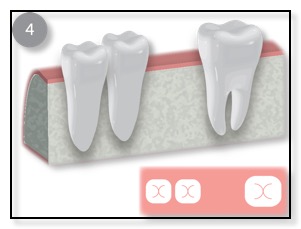

Once the bone is heal, Dr. Tsai will place the implant, allow that to integrate with the bone, and then restore with an Abutment and Crown.

The other common type of bone graft for dental implants is a Ridge Augmentation, Ridge Enhancement, or Split Ridge. (See the diagram above.) Sometimes, when a patient has lost their tooth many months or years ago, the bone in that area has resorbed (the bone is lost). The remaining bone is too thin to support the dental implant. In such cases, Dr. Tsai would numb the area where the thin wall is, gently pull the gum tissue back, pack or place the bone graft in place, and suture the gum back into place. Sometimes Dr. Tsai will “split” the ridge and pack in the bone graft in order to thicken up the bone for the implant. This procedure typically takes 4-7 months to heal. Once the bone grafting has integrated or is healed, the dental implant can be placed.